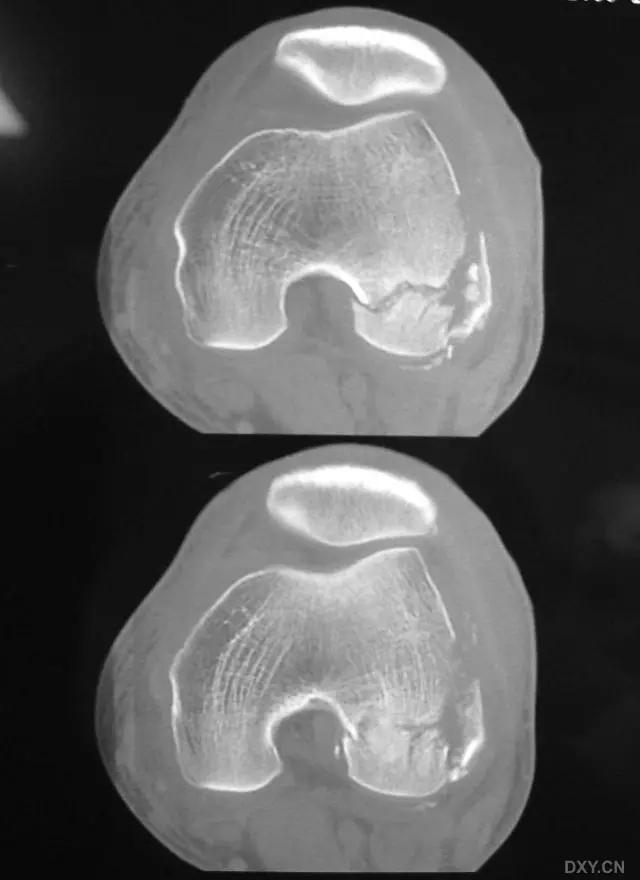

6. Pilon 骨折

涉及负重关节面(胫距关节面)与胫骨远侧干骺端的骨折。其典型特征是干骺端存在不同程度的压缩、干骺端的压缩粉碎性骨折不稳定、原发性关节软骨损伤以及永久性关节面不平整导致预后不良。

pilon 骨折正位片

pilon 骨折侧位片

pilon 骨折三维 CT 表现